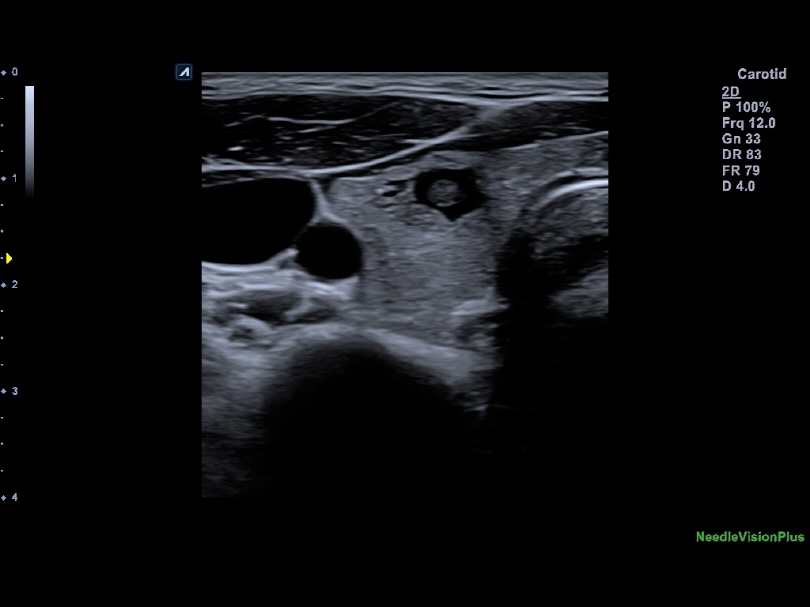

L8-17H

High density linear transducer(8-17MHz)

Application:

Breast, EM, MSK, Vascular, Small Parts

L3-12H

High density linear transducer (3-12MHz)

Application:

Breast, EM, MSK, Vascular, Small Parts

L3-12HWD

High density wide footprint linear transducer (3-12MHz)

Application:

Breast, EM, MSK, Vascular, Small Parts, Appendix

L3-12T

Linear transducer (3-12MHz)

Application:

Breast, EM, MSK, Vascular, Small Parts, Appendix